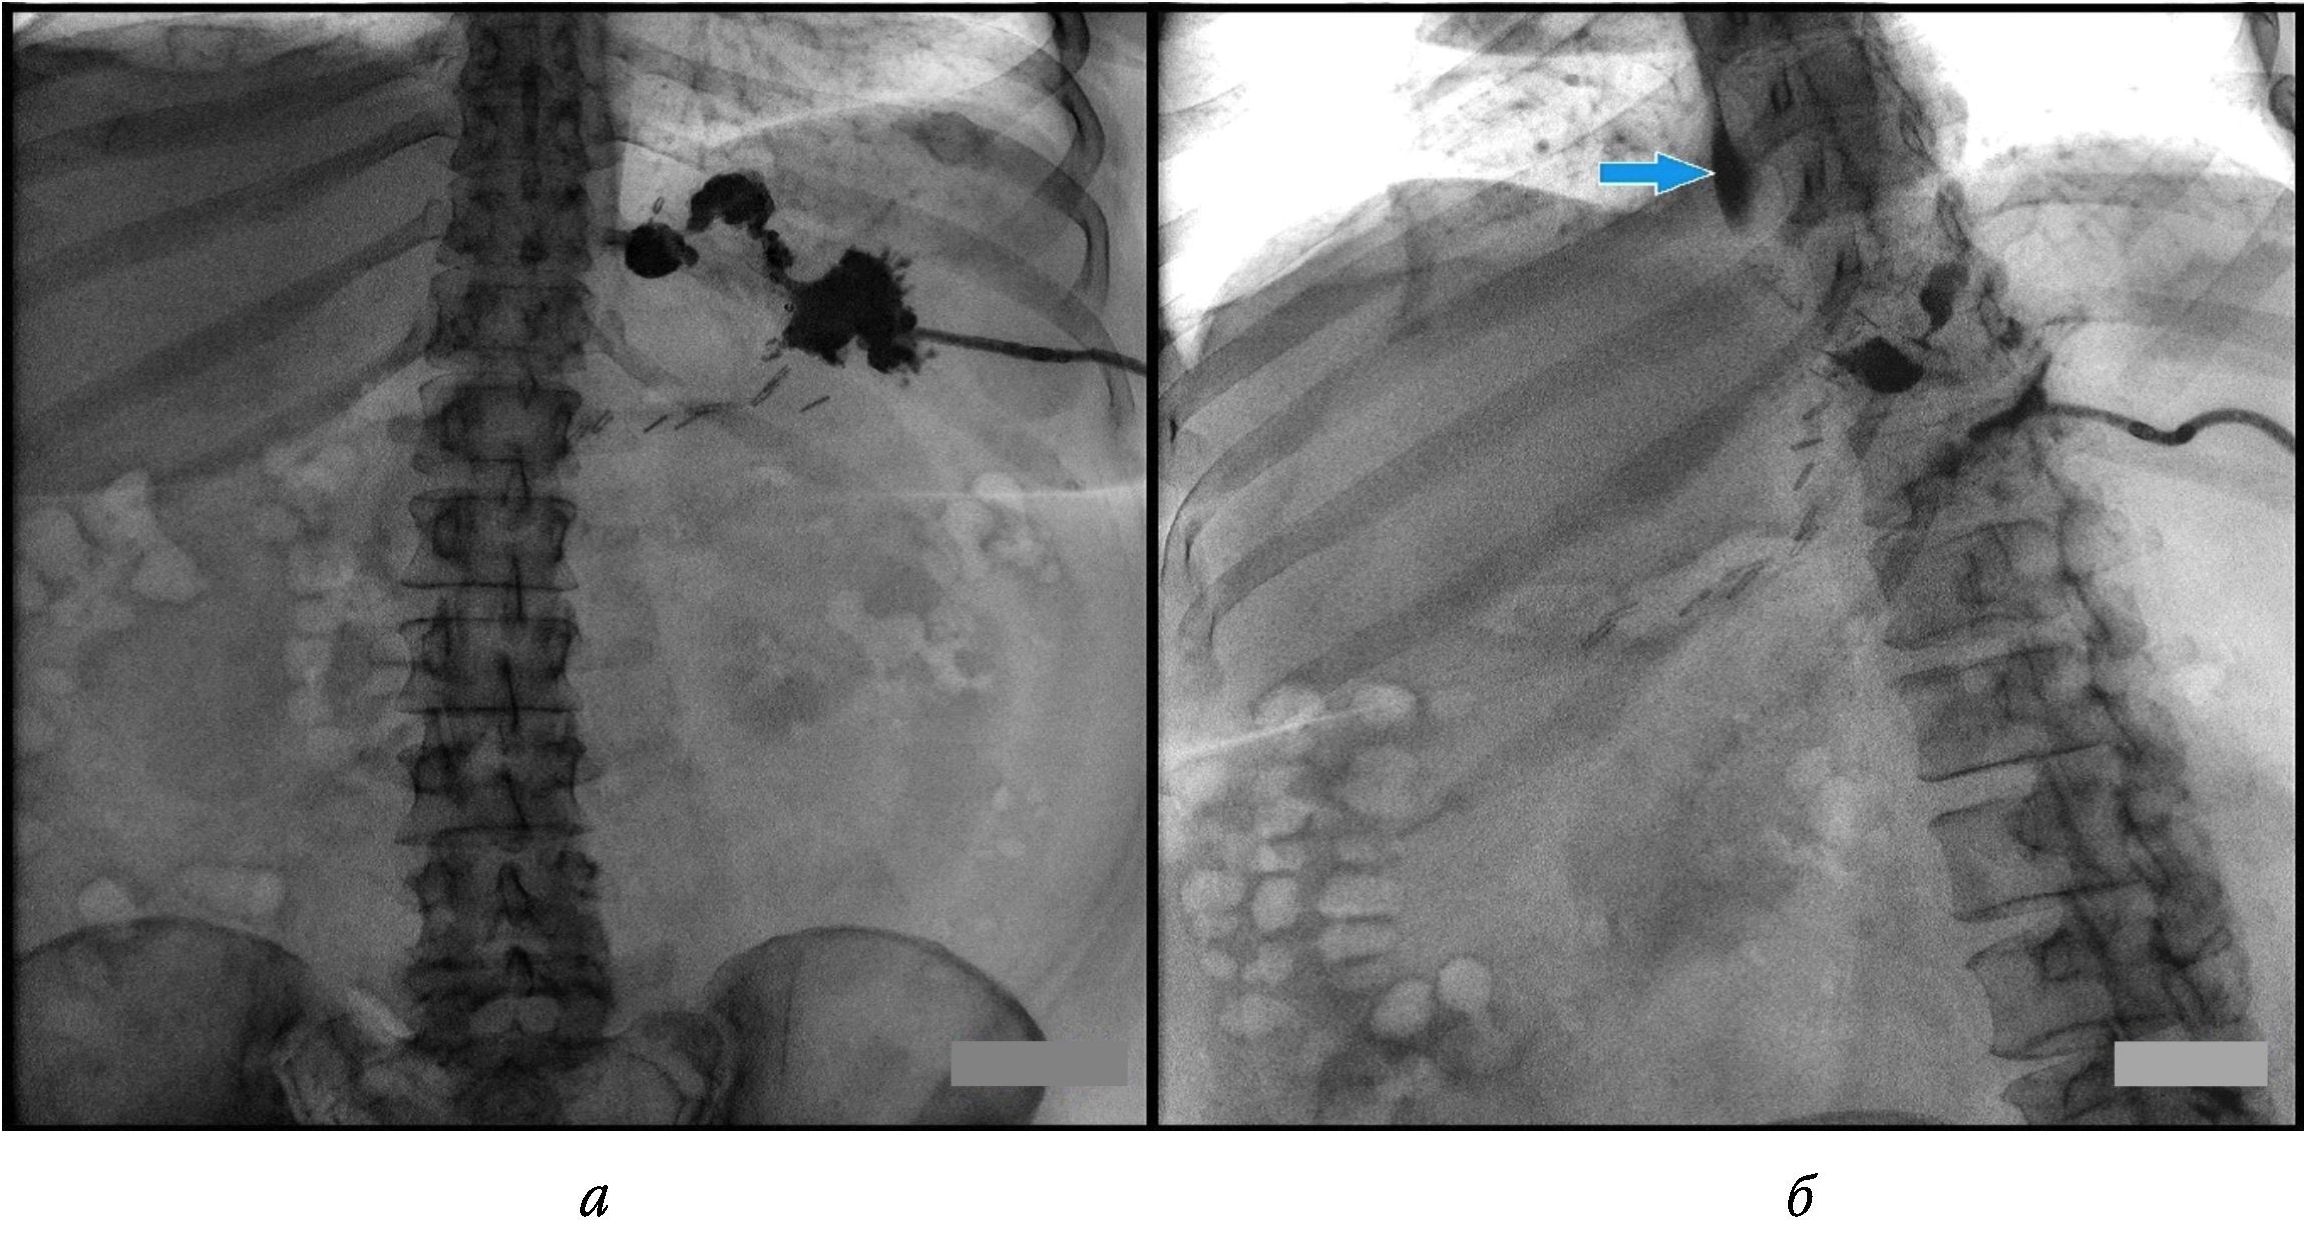

Пациентка Г., 34 года, обратилась в клинику по поводу ожирения III степени по ВОЗ (рост – 173 см, вес – 120 кг, ИМТ – 40 кг/м2). Из ассоциированных с ожирением патологических состояний диагностированы гипертоническая болезнь 2-й стадии, по артериальной гипертензии II степени, риск 3, и хронический калькулезный холецистит. Из анамнеза известно, что повышенный вес с 20-летнего возраста, предпринимала попытки снижения веса с помощью различных диет, однако похудеть не удалось. После предоперационного обследования 02.05.2023 произведена лапароскопическая продольная резекция желудка с использованием калибровочного зонда 36 Fr и аппарата Echelon 60 (две зеленые, одна желтая и три синие кассеты). Укрепления степлерной линии не проводили. В течение первых суток после операции жалоб не предъявляла, общее состояние оценивалось как удовлетворительное, объем потребляемой жидкости составил 200 мл. На вторые сутки после операции стала отмечать ноющую боль в верхних отделах живота, при этом тахикардии и перитонеальных симптомов не было, температура тела оставалась нормальной. Пациентка ходила, пила воду, у нее отходили газы и был однократный стул. Выполнено УЗИ, при котором жидкостных скоплений в брюшной полости обнаружено не было. При полипозиционном рентгенологическом исследовании пищевода и желудка с водорастворимым контрастом пассаж контрастного вещества был сохранен, его затеков за пределы органов не отмечено (рис. 1).

Рис. 1. Рентгеноскопия желудка с водорастворимым контрастом в прямой (а) и боковой (б) проекциях, в положении стоя. Данных о наличии затека за пределы контуров желудка не выявлено

По данным рентгеноскопии желудка несостоятельность линии скрепочного шва выявляется только в 28–50 % случаев [2; 11]. В нашем наблюдении при полипозиционном рентгенологическом исследовании, выполненном как после первичной операции, так и после релапароскопии, не было зафиксировано подтекания контрастного вещества за пределы желудка. Аналогичные данные по низкой эффективности рентгеноскопии желудка отражены в работах А.Г. Хитарьян и соавт. [12], Л.П. Котельниковой и соавт. [13]. Поэтому на сегодняшний день КТ с пероральным и/или внутривенным введением контраста следует рассматривать как наиболее ценный неинвазивный метод диагностики несостоятельности линии степлерного шва, что подтверждает описанный нами случай и данные литературы, свидетельствующие о 86–90%-ной информативности [14].